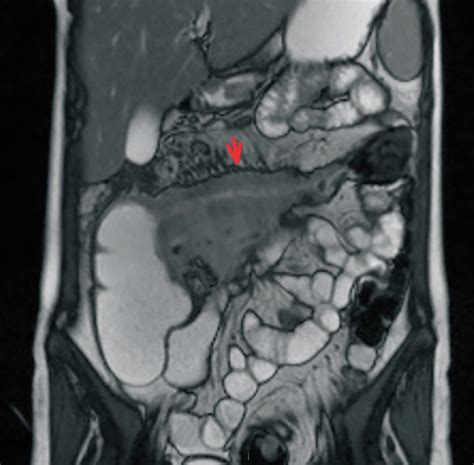

- Ultrasonografia (US), computer tomografia (CT) și rezonanța magnetică nucleară (RMN) pot evidenția îngroșarea peretelui și îngustarea lumenului intestinal.

- Aspectele radiologice tipice sunt reprezentate de „piatra de pavaj”, semnul frânghiei (segmentul ileal afectat apare stenozat și rigid cu aspect de frânghie scamoasă), ulcere fisurare și fistule.